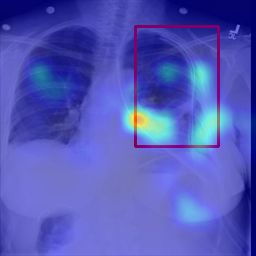

Deployments of artificial intelligence in medical diagnostics mandate not just accuracy and efficacy but also trust, emphasizing the need for explainability in machine decisions. The recent trend in automated medical image diagnostics leans towards the deployment of Transformer-based architectures, credited to their impressive capabilities. Since the self-attention feature of transformers contributes towards identifying crucial regions during the classification process, they enhance the trustability of the methods. However, the complex intricacies of these attention mechanisms may fall short of effectively pinpointing the regions of interest directly influencing AI decisions. Our research endeavors to innovate a unique attention block that underscores the correlation between 'regions' rather than 'pixels'. To address this challenge, we introduce an innovative system grounded in prototype learning, featuring an advanced self-attention mechanism that goes beyond conventional ad-hoc visual explanation techniques by offering comprehensible visual insights. A combined quantitative and qualitative methodological approach was used to demonstrate the effectiveness of the proposed method on the large-scale NIH chest X-ray dataset. Experimental results showed that our proposed method offers a promising direction for explainability, which can lead to the development of more trustable systems, which can facilitate easier and rapid adoption of such technology into routine clinics. The code is available at www.github.com/NUBagcilab/r2r_proto.